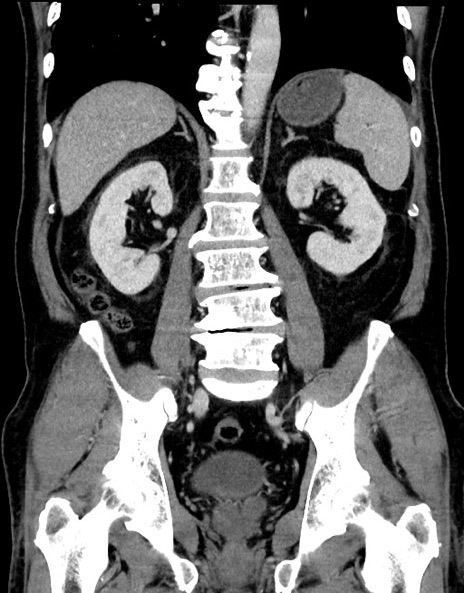

症例15(冠状断像)

【症例】70歳代男性

【主訴】腹痛

【現病歴】今朝から腹痛あり。全体的に痛い。特に左上の方。排ガスが今日はない。冷や汗が出る。

【既往歴】直腸癌術後

【身体所見】左側腹部〜上腹部に圧痛あり。腹膜刺激症状明らかなではない。軽度反跳痛。左下腹部に術後瘢痕あり。

【データ】WBC 7700、CRP 0.02